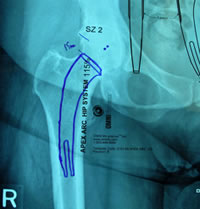

| Pre-op templating |

His own templating process |

Determining neck resection |

Photos from His First Case

Dr. Mackel has participated at cadaver training, observed live surgery and has studied and reviewed the design concept, surgical technique and attended educational seminars prior-to scheduling his first case. It is this dedication to this educational process that reduces his operative learning curve and provides his patients with the best possible clinical/surgical outcome. |

JISRF is pleased that Dr. Mackel has agreed to help define the indications and contraindications on Neck Stabilized Stems for THA and as part of that process, what are the learning curves to preoperative planning (templating). Lateral templating appears to be key in determining stem size and A/P helps to determine level of neck resection (leg length) and femoral offset. |